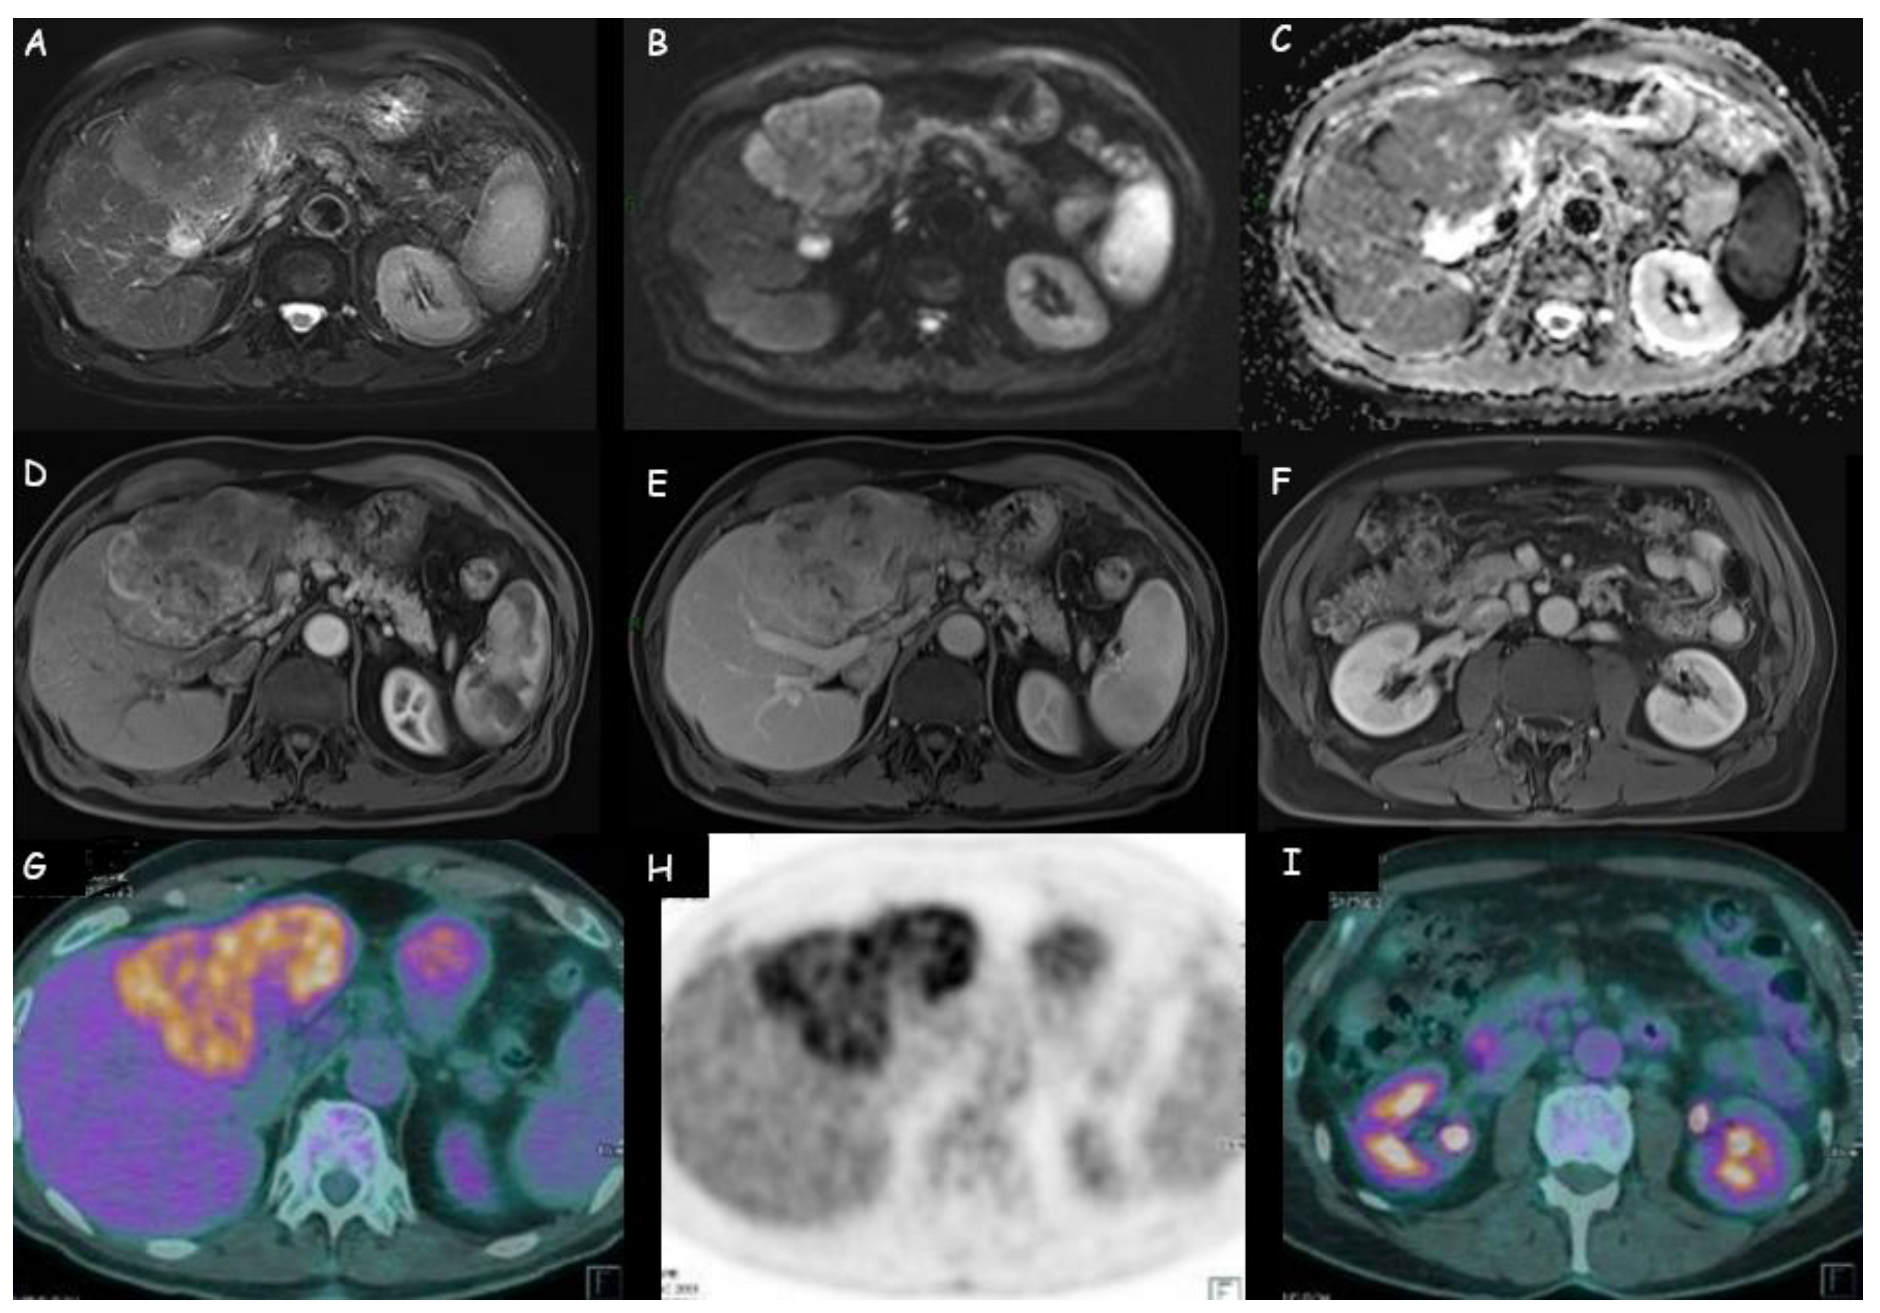

Figure 4.

(A–E) Magnetic resonance imaging of an intrahepatic cholangiocarcinoma of 11 cm × 7 cm in the left liver lobe: weak hyperdensity in T2 weighted sequences; restriction at diffusion-weighted imaging (DWI); peripheral wash-in with late central retention. (F) Lymphadenopathies in celiac, hepatic, and left paraaortic area. (G,H) Positron emission tomography with 18-fluoro-2-deoxy-d-glucose (18FDG-PET) of the same lesion: increased uptake of the metabolic agent in the hepatic hypodense lesion, with markedly inhomogeneous distribution of the radiopharmaceutical. (I) Weak uptake of the metabolic tracer in the locoregional lymph nodes.

1.3. Positron Emission Tomography with Fluorodeoxyglucose

Positron emission tomography with 18-fluoro-2-deoxy-d-glucose (18FDG-PET) is a radiologic technique that identifies neoplastic tissues based on their high glucose utilization. This technique is not adequate to provide anatomical data on the localization of a lesion: to overcome this limitation, PET/Computed Tomography (PET-CT) was developed through the combination of a full-ring PET scanner with a multidetector-row helical CT. PET-CT shows higher sensitivity than CT and MRI in the identification of metastatic lymph nodes. This method is applied in case of potentially resectable disease at CT or MRI because it can help to establish the feasibility of surgery via the refinement of lymph nodal and distant-metastases staging [26]. Moreover, it can contribute to post-treatment follow-up with a sensitivity of 85–95% in the detection of mass-forming iCCA. In the case of recurrent or metastatic CCA, PET (with or without CT) has 94% sensitivity and 100% specificity compared to 82% and 43%, respectively, of CT alone [71].

According to both EASL and AASLD guidelines, PET-CT is not adequate for primary tumor staging (T stage) due to its low accuracy but has a relevant role in the detection of iCAA metastatic lymph nodes (Figure 4) and distant metastases that are not always easily identifiable by CT or MRI (PET-CT has higher sensibility, but is less satisfactory in case of lymph nodes with a diameter inferior to 1 cm) and should be performed routinely in all patients with apparently resectable lesions [17,19]. Huang et al. documented that 18-FDG PET/CT was more effective in lymph nodal metastases identification than MRI, even if negative results could not constitute a certainty for the absence of lymph nodal metastases [57]. Regarding distant metastases, PET-CT is a reliable diagnostic method [72], but it is not useful to exclude their presence due to possible false negatives (low sensitivity and high specificity) [57]. Lamarca et al. underline that 18FDG-PET can help to detect neoplastic areas in the body, but sometimes they can also highlight false-positive findings [73]. Finally, Kim et al. reported the higher specificity and accuracy of PET-CT compared to contrast-enhanced CT in the assessment of regional lymph node metastases in patients with iCCA and extrahepatic CCA [29].